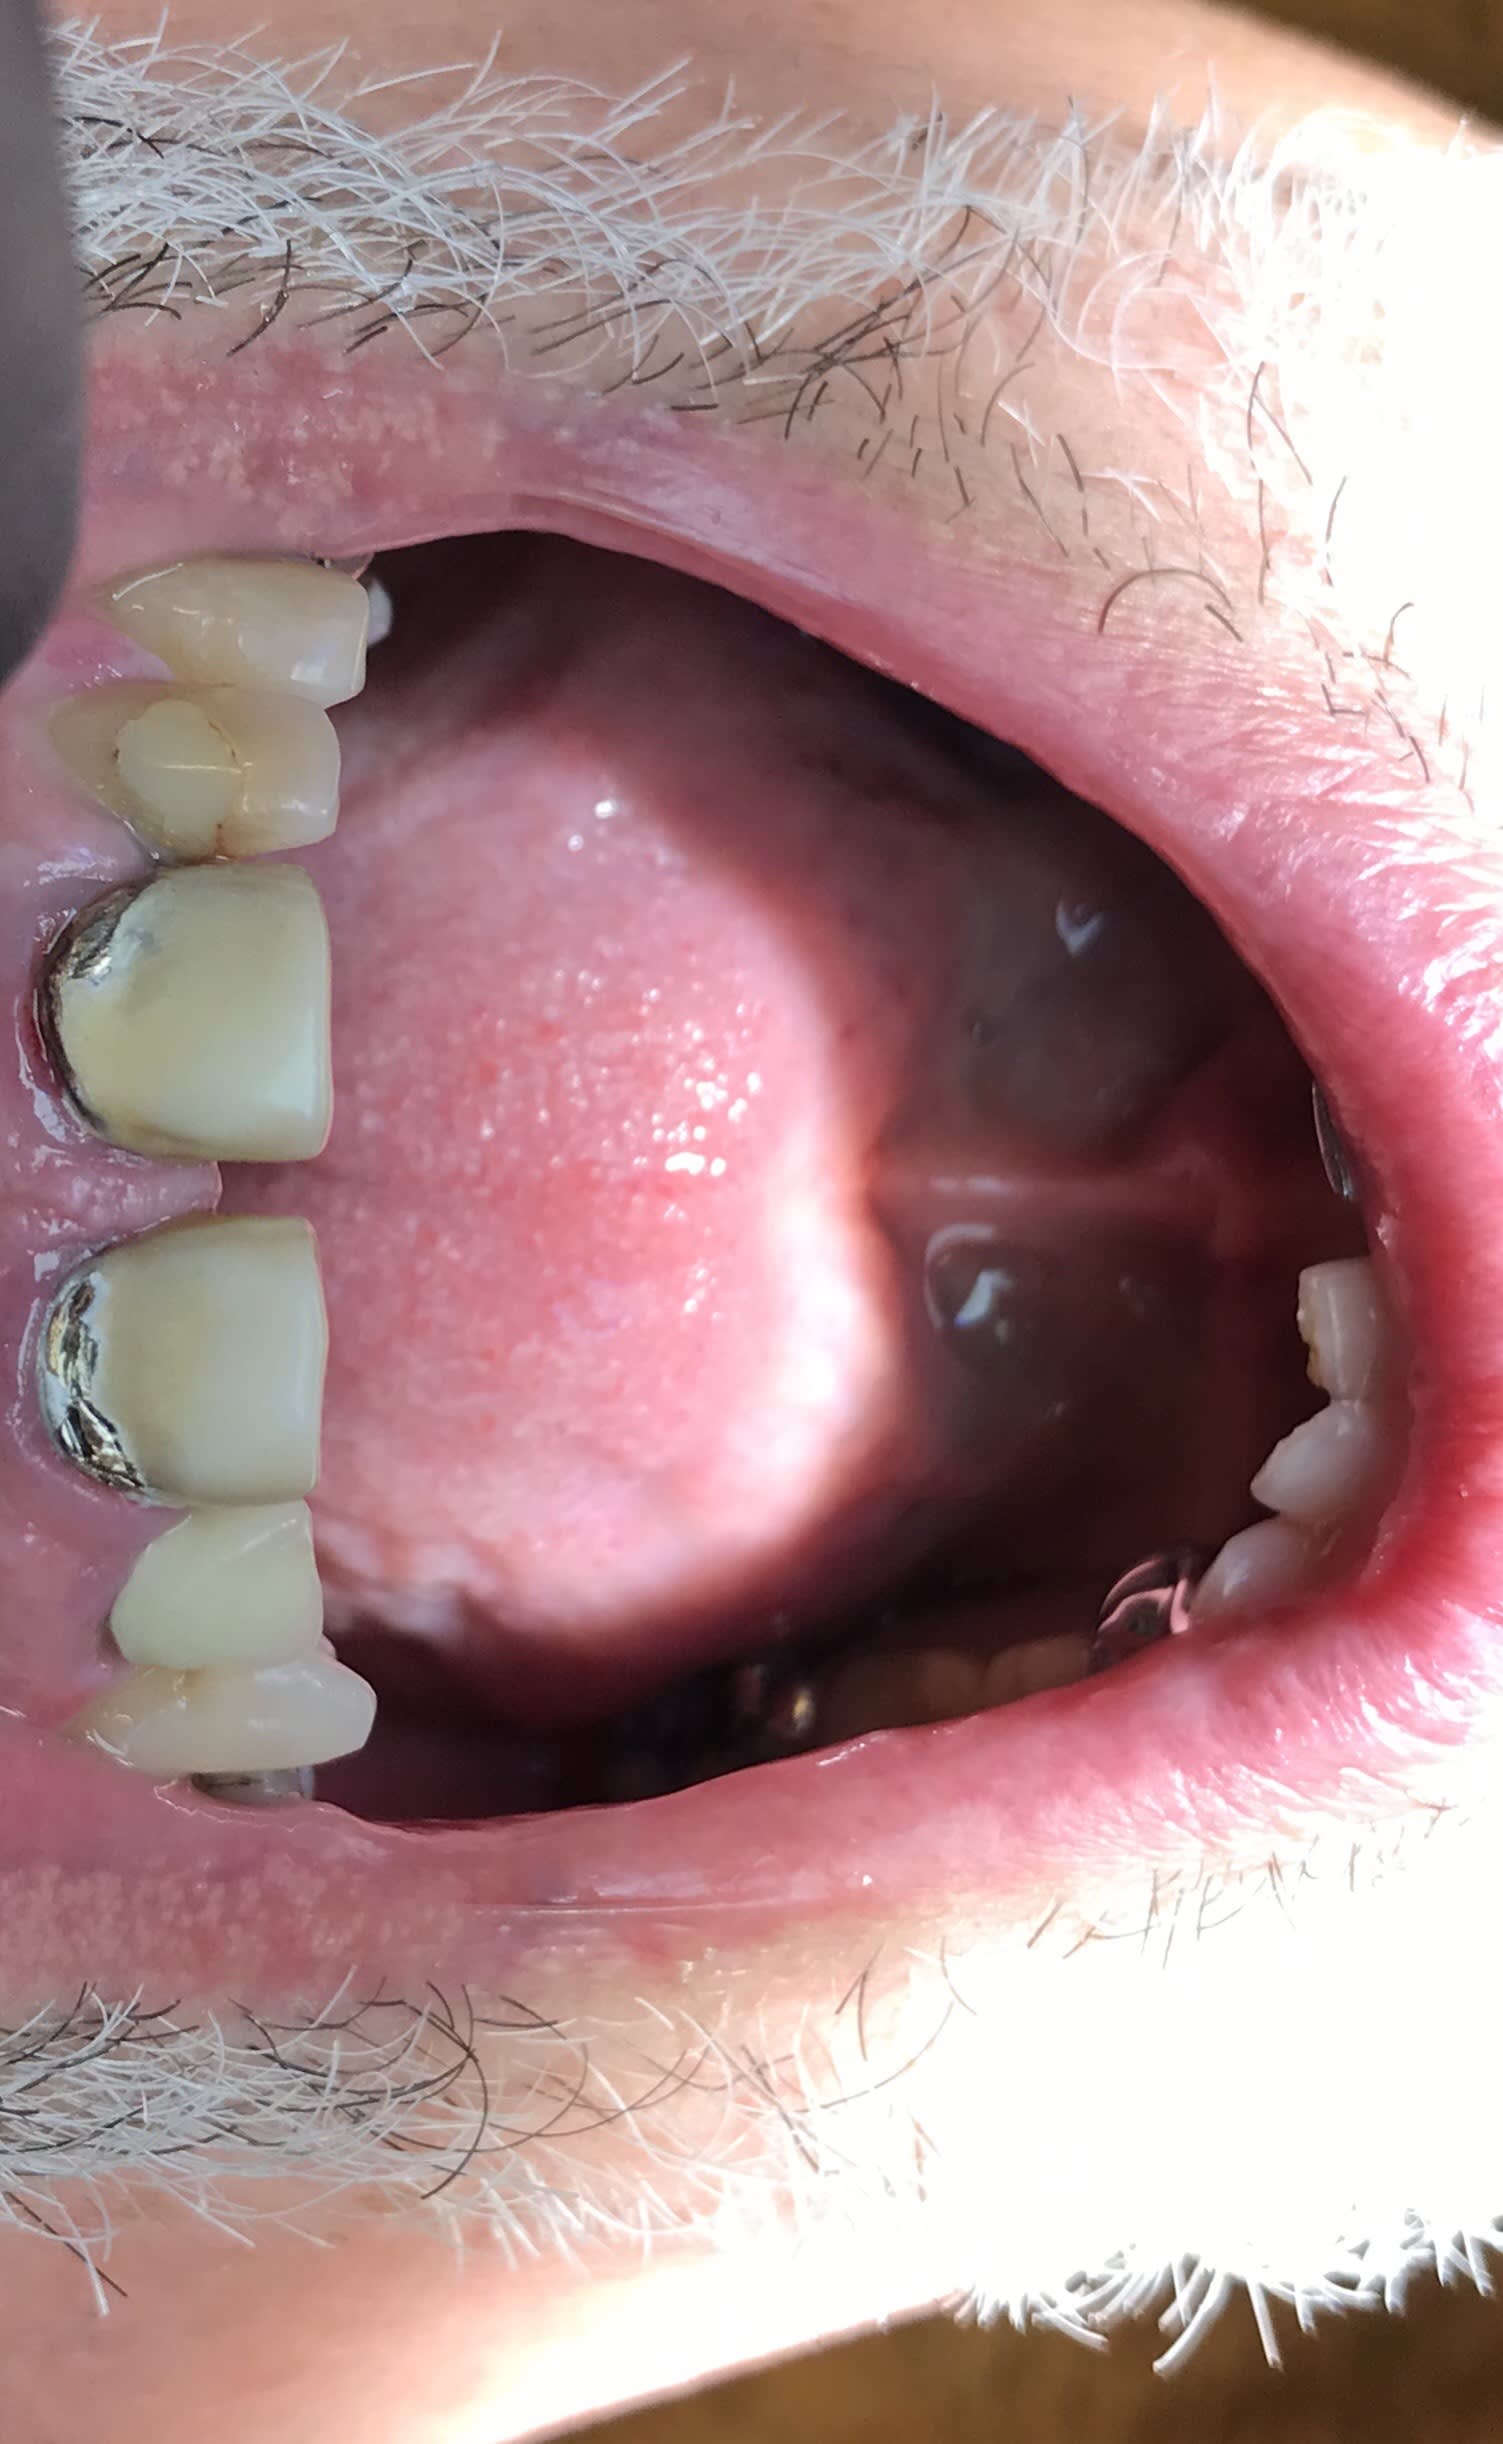

abpa8v8kp59h52klg8v2.jpg

Voir le message contenant cette image